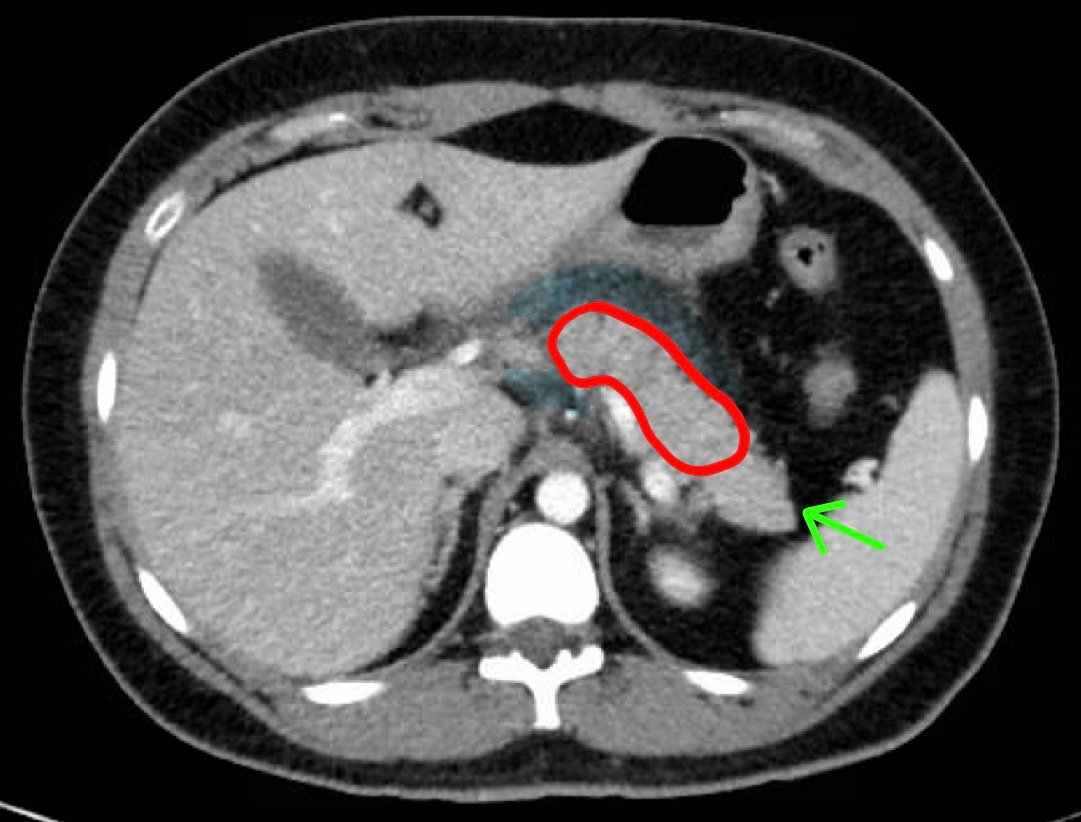

Computed tomography of the abdomen and pelvis with contrast show edema of the pancreas (red outline) and duodenum (yellow arrow) with peripancreatic inflammation, fluid and fat stranding (blue highlight). The distal pancreatic tail was noted to appear normal (green arrow). There was no organized drainable fluid collection, and no parenchymal hypo-enhancement. These findings are consistent with moderate severity acute interstitial pancreatitis.